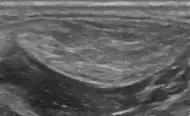

A physical exam is typically the easiest way to diagnose it. Rarely, a tissue biopsy or imaging may be required. The imaging modality of choice is magnetic resonance imaging (MRI), because it has superior sensitivity of distinguishing it from liposarcoma as well as mapping the surrounding anatomy.[20]

Medical ultrasonography of a lipoma in the thenar eminence: It is hyperechoic compared to adjacent muscle, and relatively well-defined, with miniature hyperechoic lines.[21] -